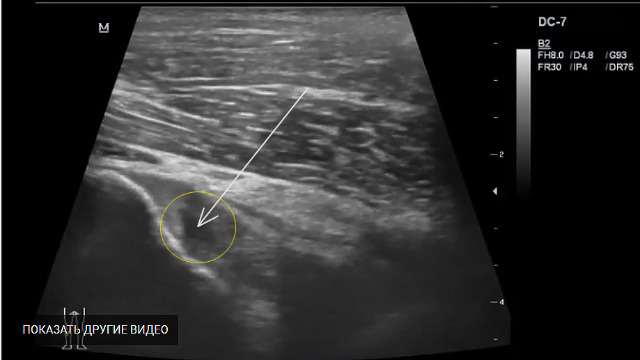

Да и гадать здесь нечего, в данном случае частичный разрыв ЗКС и ПКС в проксимальной части.

УЗИ суставов - это скрининговый метод. Как можно достоверно оценить внутрисуставные связки,когда везде в литературе говориться,что это только по МРТ судится.

Вот я по УЗИ и выставил данное заключение, теперь если кому не верится из клиницистов, пусть направляют на МРТ, как правило я редко ошибался.

Из видео четко видно, что обе связки резко утолщены и имеются несколько участко частичного разрыва.